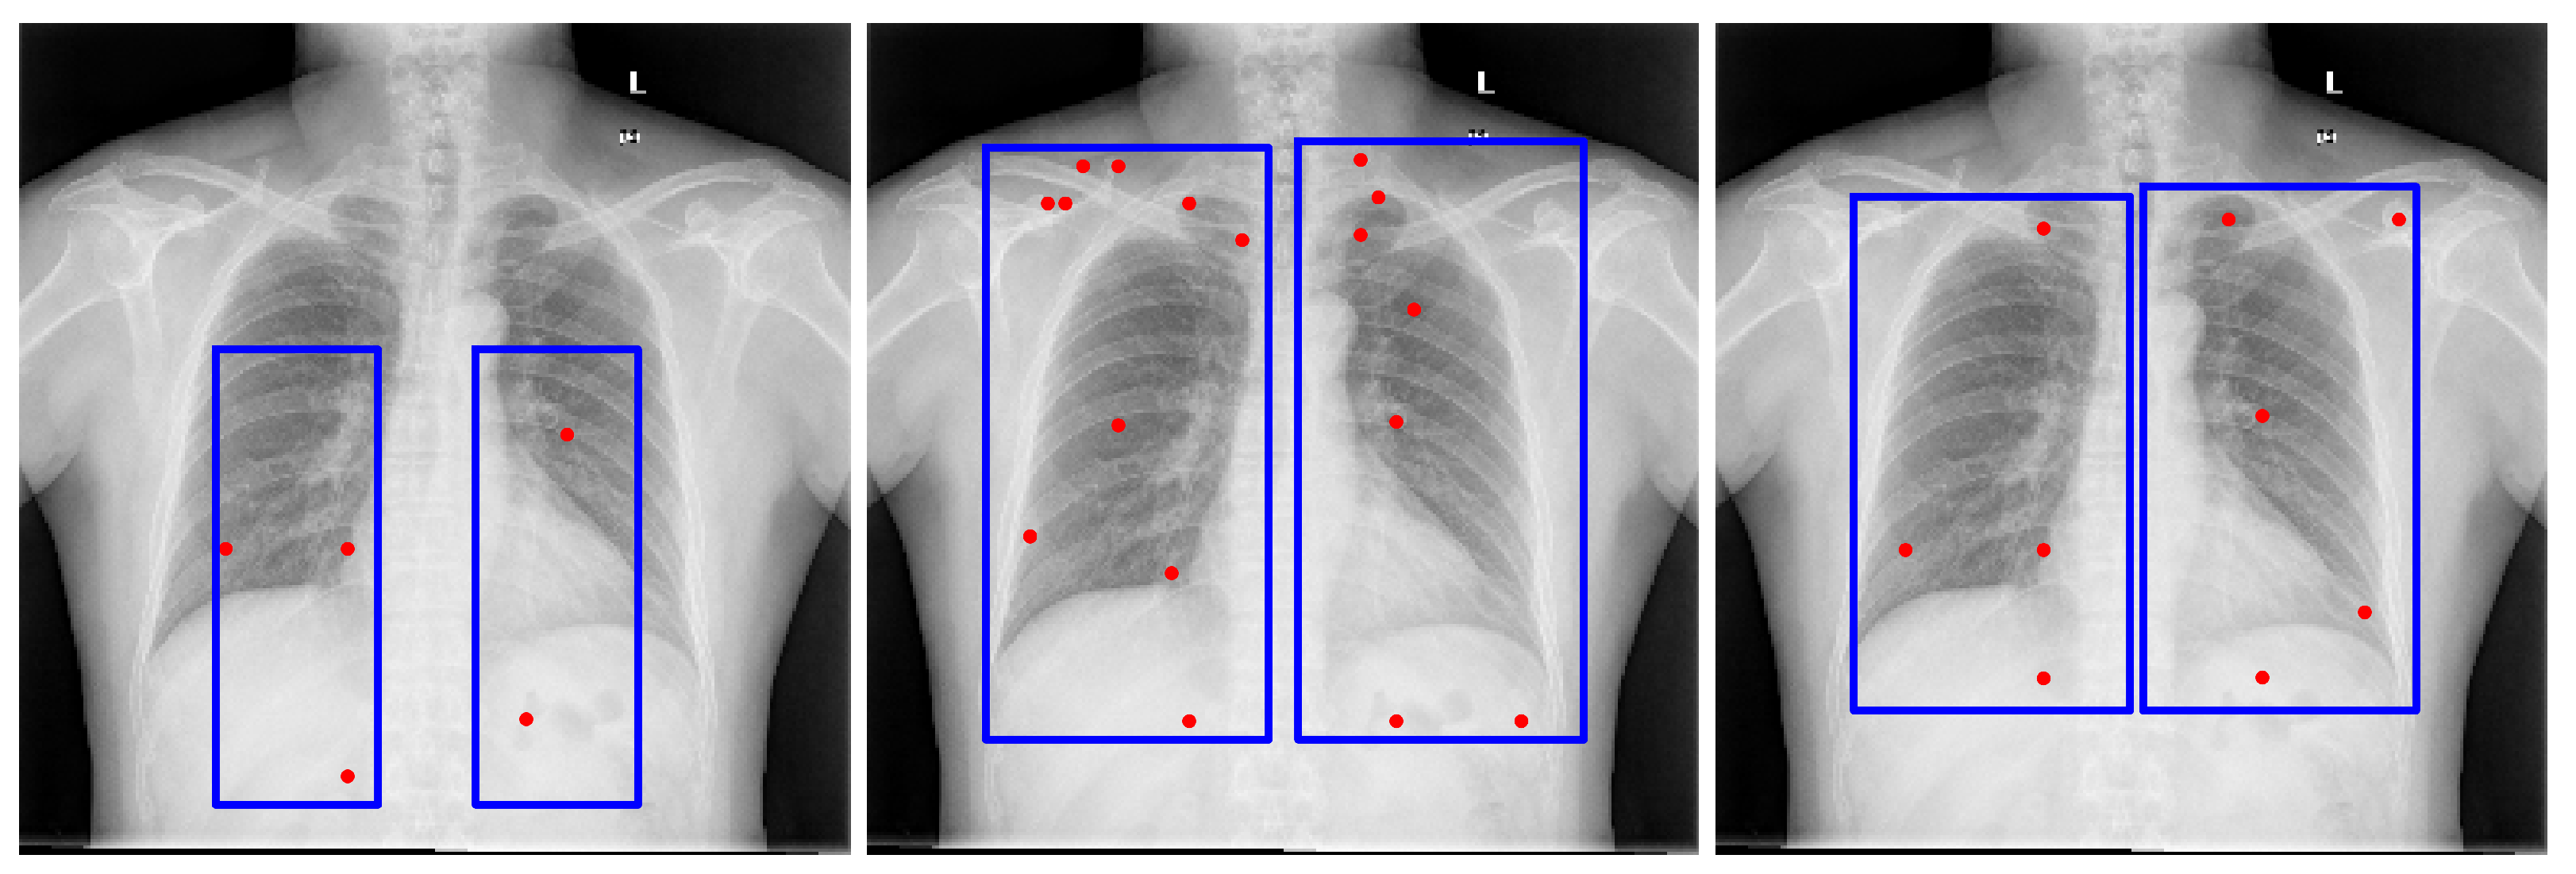

GPT-4o [13] demonstrated performance comparable to Gemini Pro 2.5 [9] in our internal evaluations; however, Gemini Pro 2.5, available from Google, was chosen for downstream experiments due to its consistent accuracy, stable API access, and available research funding for sustained API usage. It also outperformed LLaMA-based models, as shown in Figure 2. Model outputs were returned in JSON format and integrated directly into our segmentation pipeline. While the bounding box estimations generated by Gemini across multiple datasets were not sufficiently precise to serve as final segmentations, they consistently localized the region of interest. Despite occasional boundary inaccuracies, these estimations provided reliable spatial priors that effectively guided the SAM model towards more accurate segmentations, as illustrated in Figure 3.

4.5.4. Prompt Engineering and Choice of Large Vision-Language Models for Bounding Box Estimation

To derive reliable bounding box priors, we designed structured prompts that explicitly defined both the target anatomical structures and the spatial constraints of the bounding box. The final prompts used in our pipeline are provided in Appendix B. These prompts were tested across several LVLMs, including maverick-llama-4, GPT-4V, and Gemini Vision. While multiple models could generate bounding boxes, we selected Gemini Pro 2.5 for its consistent alignment with regions of interest and compatibility with available computational resources. In contrast, alternative models often produced loose or misaligned boxes, which degraded downstream segmentation accuracy. Representative bounding box results from different models with the same prompt are shown in Figure 2, underscoring the importance of prompt engineering and the sensitivity of the pipeline to LVLM choice.

Figure 2. Examples of lung bounding box estimations generated by different models: LLaMA-4-Maverick-17B-128E, GPT-4o, and Gemini Pro 2.5. The blue rectangles indicate the bounding-box prompts, and the red dots represent the point prompts. Both are provided as inputs to the Segment Anything Model (SAM) to generate segmentation candidates.